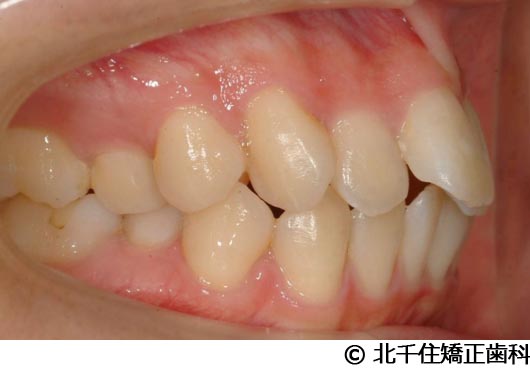

【症例4】下顎前突

- 治療前

- 治療後

- 治療名

- 下顎前突

- 費用

- 1,226,000円(税込)

- 期間

- 2年10ヵ月

- 治療回数

- 32回

- 通院頻度

- 1ヵ月ごと

- 年齢・性別

- 28歳5ヵ月・女性(初診時)

治療内容

-

患者様の症状

主訴:デコボコ、笑顔のとき歯がきれいに見えるようにしたい

治療方法

骨格性の下顎前突および開咬、上顎第二小臼歯と下顎第一小臼歯4本抜歯してワイヤー矯正(セラミックブラケット)。

治療結果

骨格性下顎前突および開咬に対し、抜歯を併用した矯正治療により歯列および咬合関係の調整を行った症例である。治療後は保定装置を使用し、歯列および咬合の安定維持を目的として定期的な経過観察を行っている。

※治療結果は個人差があります。

治療を行う上での注意点(リスク・副作用)

歯磨き不良に伴うカリエスや歯周病、歯根吸収など。